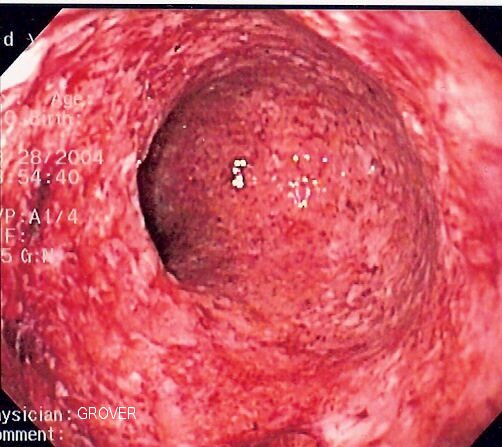

Gastroskopia to rodzaj badania endoskopowegoendoskopowego górnego odcinka przewodu pokarmowego, które polega na wprowadzeniu do przełyku przewodu rejestrującego i przekazującego obraz z wnętrza ciała pacjenta. Badanie umożliwia obserwację zmian na powierzchni przełyku, żołądka i dwunastnicy. W jego trakcie lekarz może pobrać fragment błony śluzowej w celu dalszego badania histopatologicznegobadania histopatologicznego zlokalizowanych zmian. Dzięki gastroskopii możliwe jest wczesne wykrycie wrzodów żołądka i dwunastnicy, nowotworów i zmian zapalnych, a także obecności bakterii Helicobacter pylori.

Kolonoskopia jest ważnym badaniem endoskopowym wykonywanym w profilaktyce raka jelita grubego. Polega na wprowadzeniu przez odbyt giętkiego przyrządu zakończonego kamerą (kolonoskopu). Umożliwia to obserwację ścian i pobieranie wycinków błony śluzowej jelita grubego do badań histopatologicznych, a także wykonywanie drobnych zabiegów, jak np. usunięcie polipów, lub ostrzyknięcie środkami hamującymi krwawienie. Jest podstawową metodą diagnostyczną w chorobach jelita grubego, w tym nowotworów.

Badania diagnostyczne takie jak gastroskopia, kolonoskopia i USG jamy brzusznej odgrywają kluczową rolę w wczesnym wykrywaniu nieprawidłowości, umożliwiając diagnozowanie stanów zapalnych, nadżerek, polipów czy guzów. Regularne wykonywanie tych badań jest istotne w profilaktyce chorób nowotworowych przewodu pokarmowego, szczególnie raka żołądka i raka jelita grubego.